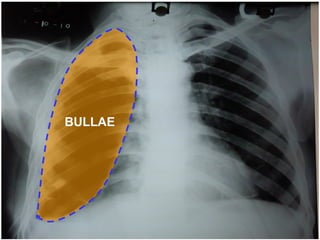

CHEST X RAY PA VIEW ADEQUATE INSPIRATION CENTRING, PATIENT POSITION -  NORMAL EXPOSURE/PENETRATION -  ADEQUQTE TRACHEA POSITION -  MIDLINE HEART AND MEDIASTINUM –  NORMAL PLEURAL SPACE  –  HYDROPNEUMOTHORAX  ON THE LEFT SIDE  EVIDENCED BY THE CONVEX  OUTSIDE BORDER OF  LUNG WITH VISCERAL PLEURA AND AIR FLUID LEVEL ? BULLAE/ ?LOCULATED HYDROPNEUMOTHORAX  SEEN  ON RIGHT SIDE EVIDENCED BY CONVEX INWARDS  MARGINS OF THEIR WALLS WITH AIR FLUID LEVEL COSTOPHRENIC ANGLES  BLUNTED BILATERALLY  CARDIOPHRENIC ANGLES  FREE HILA DENSITY, POSITION, SHAPE -  NORMAL SOFT TISSUES –  NORMAL BONES-  NORMAL Imp:LEFT HYDROPNEUMOTHORAX  RIGHT BULLOUS DISEASE/HYDROPNEUMOTHORAX WITH ?PLEURAL THICKENING

CT CHEST AFTER 10 DAYS RIGHT HYDROPNEUMOTHORAX EMPHYSEMATOUS BULLAE IN B/L LOWER LOBE, RIGHT MIDDLE LOBE B/L LOWER LOBE BRONCHIECTASIS

BULLAE

CHEST X RAYPA VIEW ADEQUATE INSPIRATION CENTRING, PATIENT POSITION - NORMAL EXPOSURE/PENETRATION - ADEQUQTE TRACHEA POSITION - MIDLINE HEART AND MEDIASTINUM – NORMAL PLEURAL SPACE – HYDROPNEUMOTHORAX ON THE LEFT SIDE EVIDENCED BY THE CONVEX OUTSIDE BORDER OF LUNG WITH VISCERAL PLEURA AND AIR FLUID LEVEL ? BULLAE/ ?LOCULATED HYDROPNEUMOTHORAX SEEN ON RIGHT SIDE EVIDENCED BY CONVEX INWARDS MARGINS OF THEIR WALLS WITH AIR FLUID LEVEL COSTOPHRENIC ANGLES BLUNTED BILATERALLY CARDIOPHRENIC ANGLES FREE HILA DENSITY, POSITION, SHAPE - NORMAL SOFT TISSUES – NORMAL BONES- NORMAL Imp:LEFT HYDROPNEUMOTHORAX RIGHT BULLOUS DISEASE/HYDROPNEUMOTHORAX WITH ?PLEURAL THICKENING

CT CHEST AFTER10 DAYS RIGHT HYDROPNEUMOTHORAX EMPHYSEMATOUS BULLAE IN B/L LOWER LOBE, RIGHT MIDDLE LOBE B/L LOWER LOBE BRONCHIECTASIS